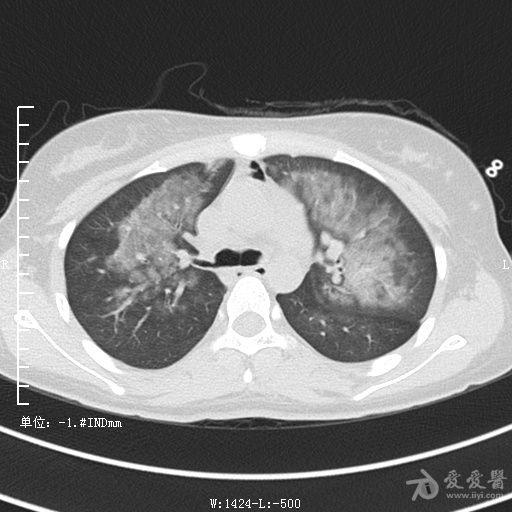

典型支气管扩张及肺水肿CT片

典型支气管扩张肺水肿